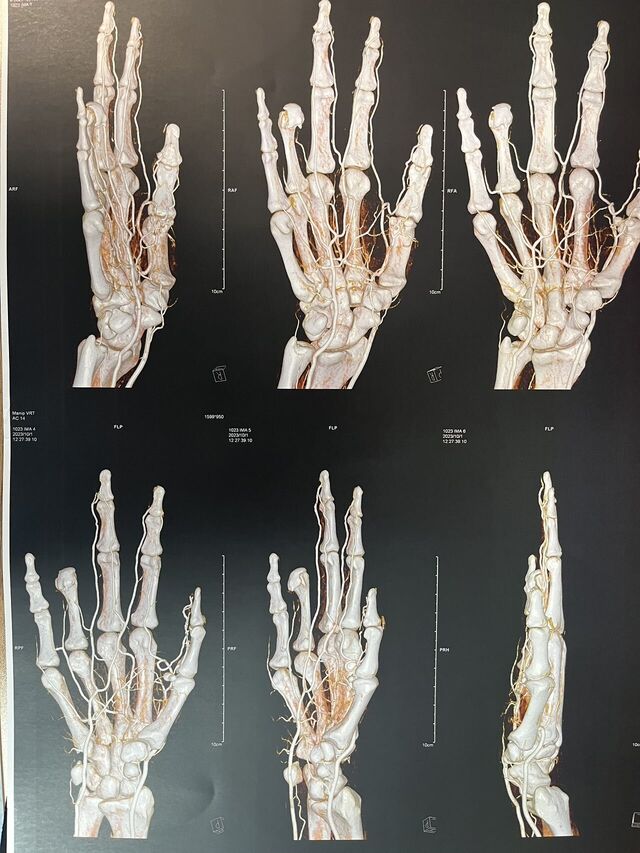

楼主| 发表于 2023-10-15 18:21:05 | 显示全部楼层

示指再造 1.5月随访

微信图片_20231011185314.jpg 微信图片_20231011185317.jpg 微信图片_20231011185255.jpg 微信图片_20231011185259.jpg 微信图片_20231011185303.jpg 微信图片_20231011185310.jpg 微信图片_20231011185557.jpg 微信图片_20231011185307.jpg